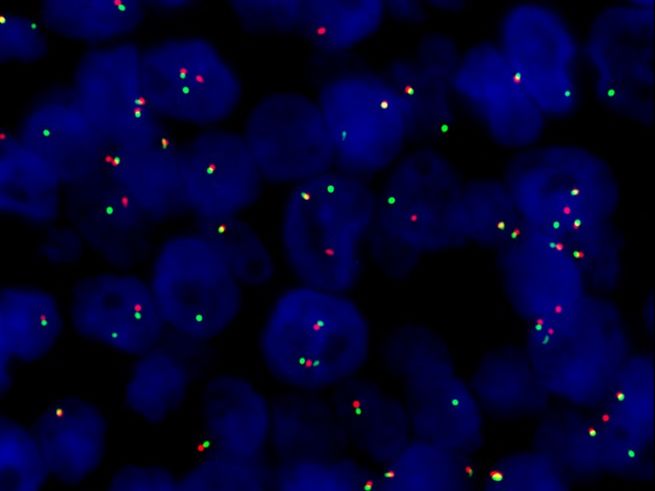

La pathologie est une discipline médicale à la fois fondamentale et clinique. Au sens strict, nous analysons des tissus, c'est-à-dire des biopsies ou des pièces opératoires, ainsi que des cellules – on parle respectivement d’examens histologiques ou cytologiques -, afin de poser un diagnostic aussi précis que possible à partir des lésions observées au microscope. Aujourd’hui, dans de nombreuses situations, nous complétons cette analyse par des techniques plus pointues, notamment en immunohistochimie et en biologie moléculaire, afin de préciser encore mieux le diagnostic et d’apporter des éléments supplémentaires pour la prise en charge thérapeutique.

Enfin, la pathologie moléculaire intervient en deuxième ligne pour des analyses complémentaires, avec trois laboratoires principaux, immunohistochimie, FISH et biologie moléculaire. À noter que nous disposons aussi d’un microscope électronique, indispensable pour certaines indications très spécialisées, notamment l’analyse des biopsies rénales.